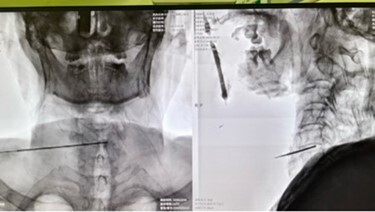

今年2月,患者来到湘雅三医院疼痛科就诊。入院后,医生团队考虑到王爹年龄较大,慢性阻塞性肺疾病合并心功能不全,不能耐受传统开放手术,胡蓉组织科室医护人员行详细的术前讨论,最后选择在静脉麻醉(鼻咽通气道辅助通气)下为其行经皮穿刺颈椎间盘激光修复术。

2月底,手术团队顺利为患者进行手术,术中在超声和C臂联合引导下,经皮细针穿刺进入责任椎间盘,利用970nm波长低能量激光进行椎间盘的汽化和修复,并促进软骨化生,最终达到椎间盘减压和镇痛的目的。患者伤口仅为一个针眼,出血量极少。术后王爹随即感觉右肩和右臂轻松不少,当天晚上便能下床行走。术后第二天王爹疼痛基本缓解,胃口大开,近日已从该院疼痛科康复出院。